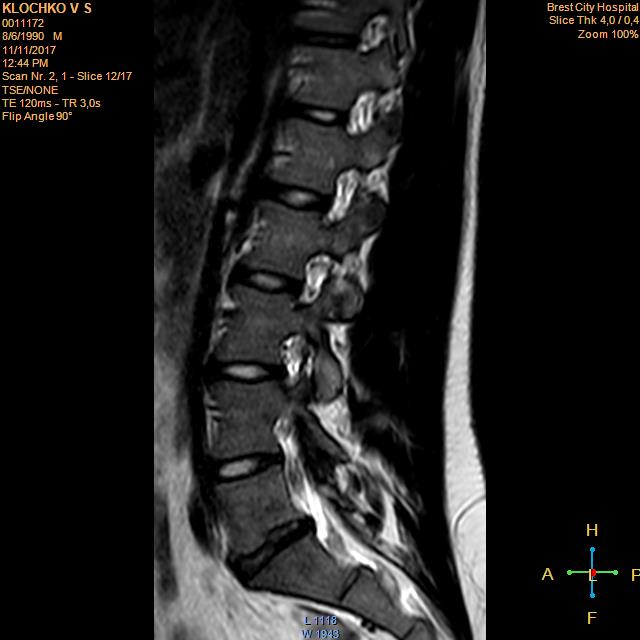

Тренировки с межпозвоночной грыжей.